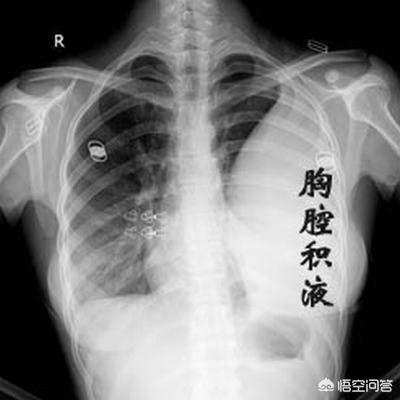

1) L'insuffisance respiratoire, communément appelée manque d'air du patient, est la plus fréquente chez les patients atteints d'un cancer du poumon avancé. Le cancer central du poumon obstrue la trachée et les bronches principales, ce qui rend difficile l'entrée de l'air, et en cas d'atélectasie pulmonaire importante, le patient souffrira progressivement d'essoufflement et de dyspnée. Certains patients développent un épanchement pleural important dû à des métastases pleurales, qui comprime les tissus pulmonaires et empêche la réouverture des poumons. Chez d'autres patients, les lésions pulmonaires sont trop nombreuses et la surface effective de la membrane respiratoire est considérablement réduite. Toutes ces raisons finissent par entraîner une oppression thoracique, un essoufflement, une respiration assise et, finalement, une insuffisance respiratoire.

Ce patient n'avait que 39 ans, souffrait d'oppression thoracique et d'essoufflement, et on lui a diagnostiqué un adénocarcinome du côté droit du poumon, avec un épanchement pleural important et une perte de fonction de l'ensemble du poumon droit. Une affection aussi grave est plus fréquente chez les personnes âgées et, si elle n'est pas traitée, une insuffisance respiratoire se produira rapidement. Heureusement, elle est sensible à la thérapie ciblée et vit avec la tumeur depuis plus de trois ans maintenant, avec un épanchement pleural sous contrôle.

4. l'épanchement pleural

L'épanchement pleural est une autre complication fréquente chez les patients atteints d'un cancer du poumon, et un épanchement pleural important peut entraîner des difficultés respiratoires chez les patients.

- Lorsque le cancer du poumon métastase dans la poitrine, un épanchement pleural, en particulier un épanchement pleural sanglant, peut se produire et, à ce moment-là, une toux de sang peut survenir.